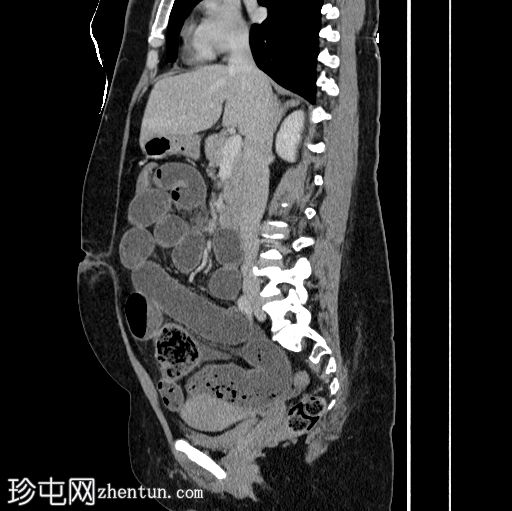

冠状位增强扫描(门静脉期)

小肠袢扩张,远端回肠袢可见粪便样改变,提示移行点就在附近。移行点远端可见回​​肠塌陷。

在移行点近端,肠系膜对侧缘可见一盲端管状结构,符合梅克尔憩室的特征。

少量游离液体。